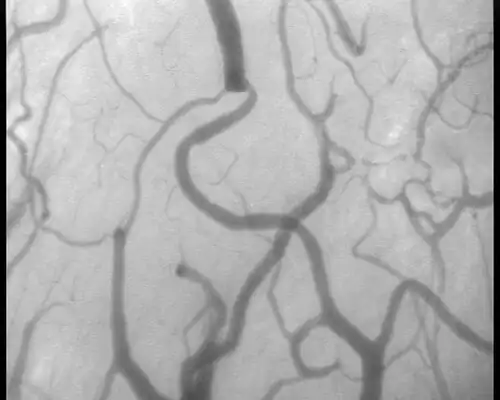

Als sidestream dark field imaging (abgekürzt SDF, zu deutsch: Seitenstrom-Dunkelfeld-Bildgebung) wird ein Verfahren zur Untersuchung der Mikrozirkulation bezeichnet, also zur Untersuchung kleiner und kleinster Blutgefäße. Das Verfahren wird mit einem kleinen Gerät durchgeführt, mit dem solche Gefäße bei Patienten zum Beispiel unter der Zunge untersucht werden können, wo keine störenden Hautschichten vorhanden sind. Die Technik verwendet einen zentralen Lichtleiter, in dem eine Linse das Bild des Präparats auf einen Kamerachip projiziert. Aus einem Ring um den zentralen Lichtleiter herum wird das Licht von grünen Leuchtdioden (Wellenlänge 530 nm) auf das Präparat eingestrahlt.[26][27]

Durch die Streuung im Präparat kommt es zu einer gleichmäßigen Verteilung des Lichts im beobachteten Bereich, so dass eine Art Hintergrundbeleuchtung entsteht. Das Hämoglobin in den roten Blutkörperchen absorbiert grünes Licht sehr stark, so dass sich die Blutgefäße, die dicht mit roten Blutkörperchen gefüllt sind, als dunkle Strukturen vor einem erhellten Hintergrund abheben. Die maximale Eindringtiefe ins Gewebe liegt bei 500 Mikrometern.[26][27]